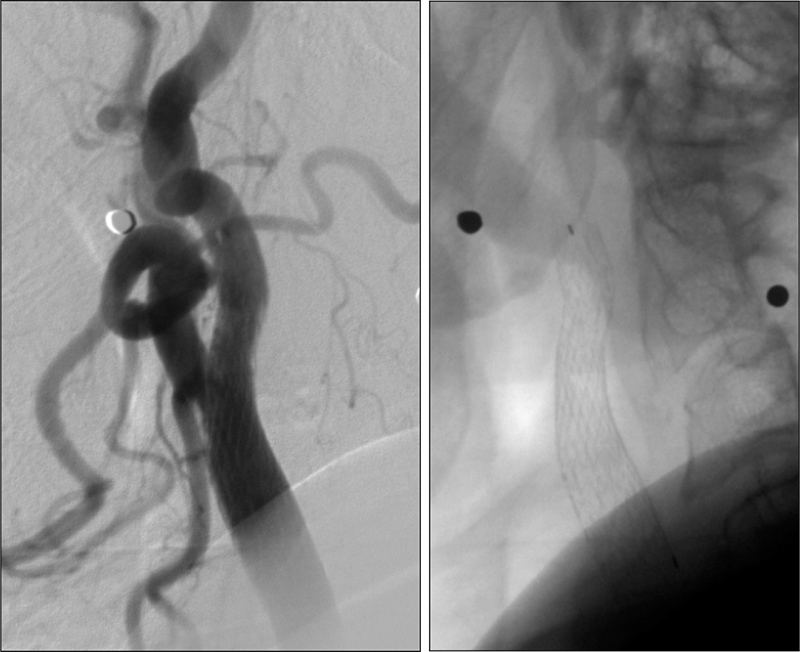

Εικόνα 3: Αποκατάσταση της στενώσεως του καρωτιδικού βολβού μετά την  τοποθέτηση stent closed-cell και αφαίρεση του συστήματος ΜΟΜΑ.

03